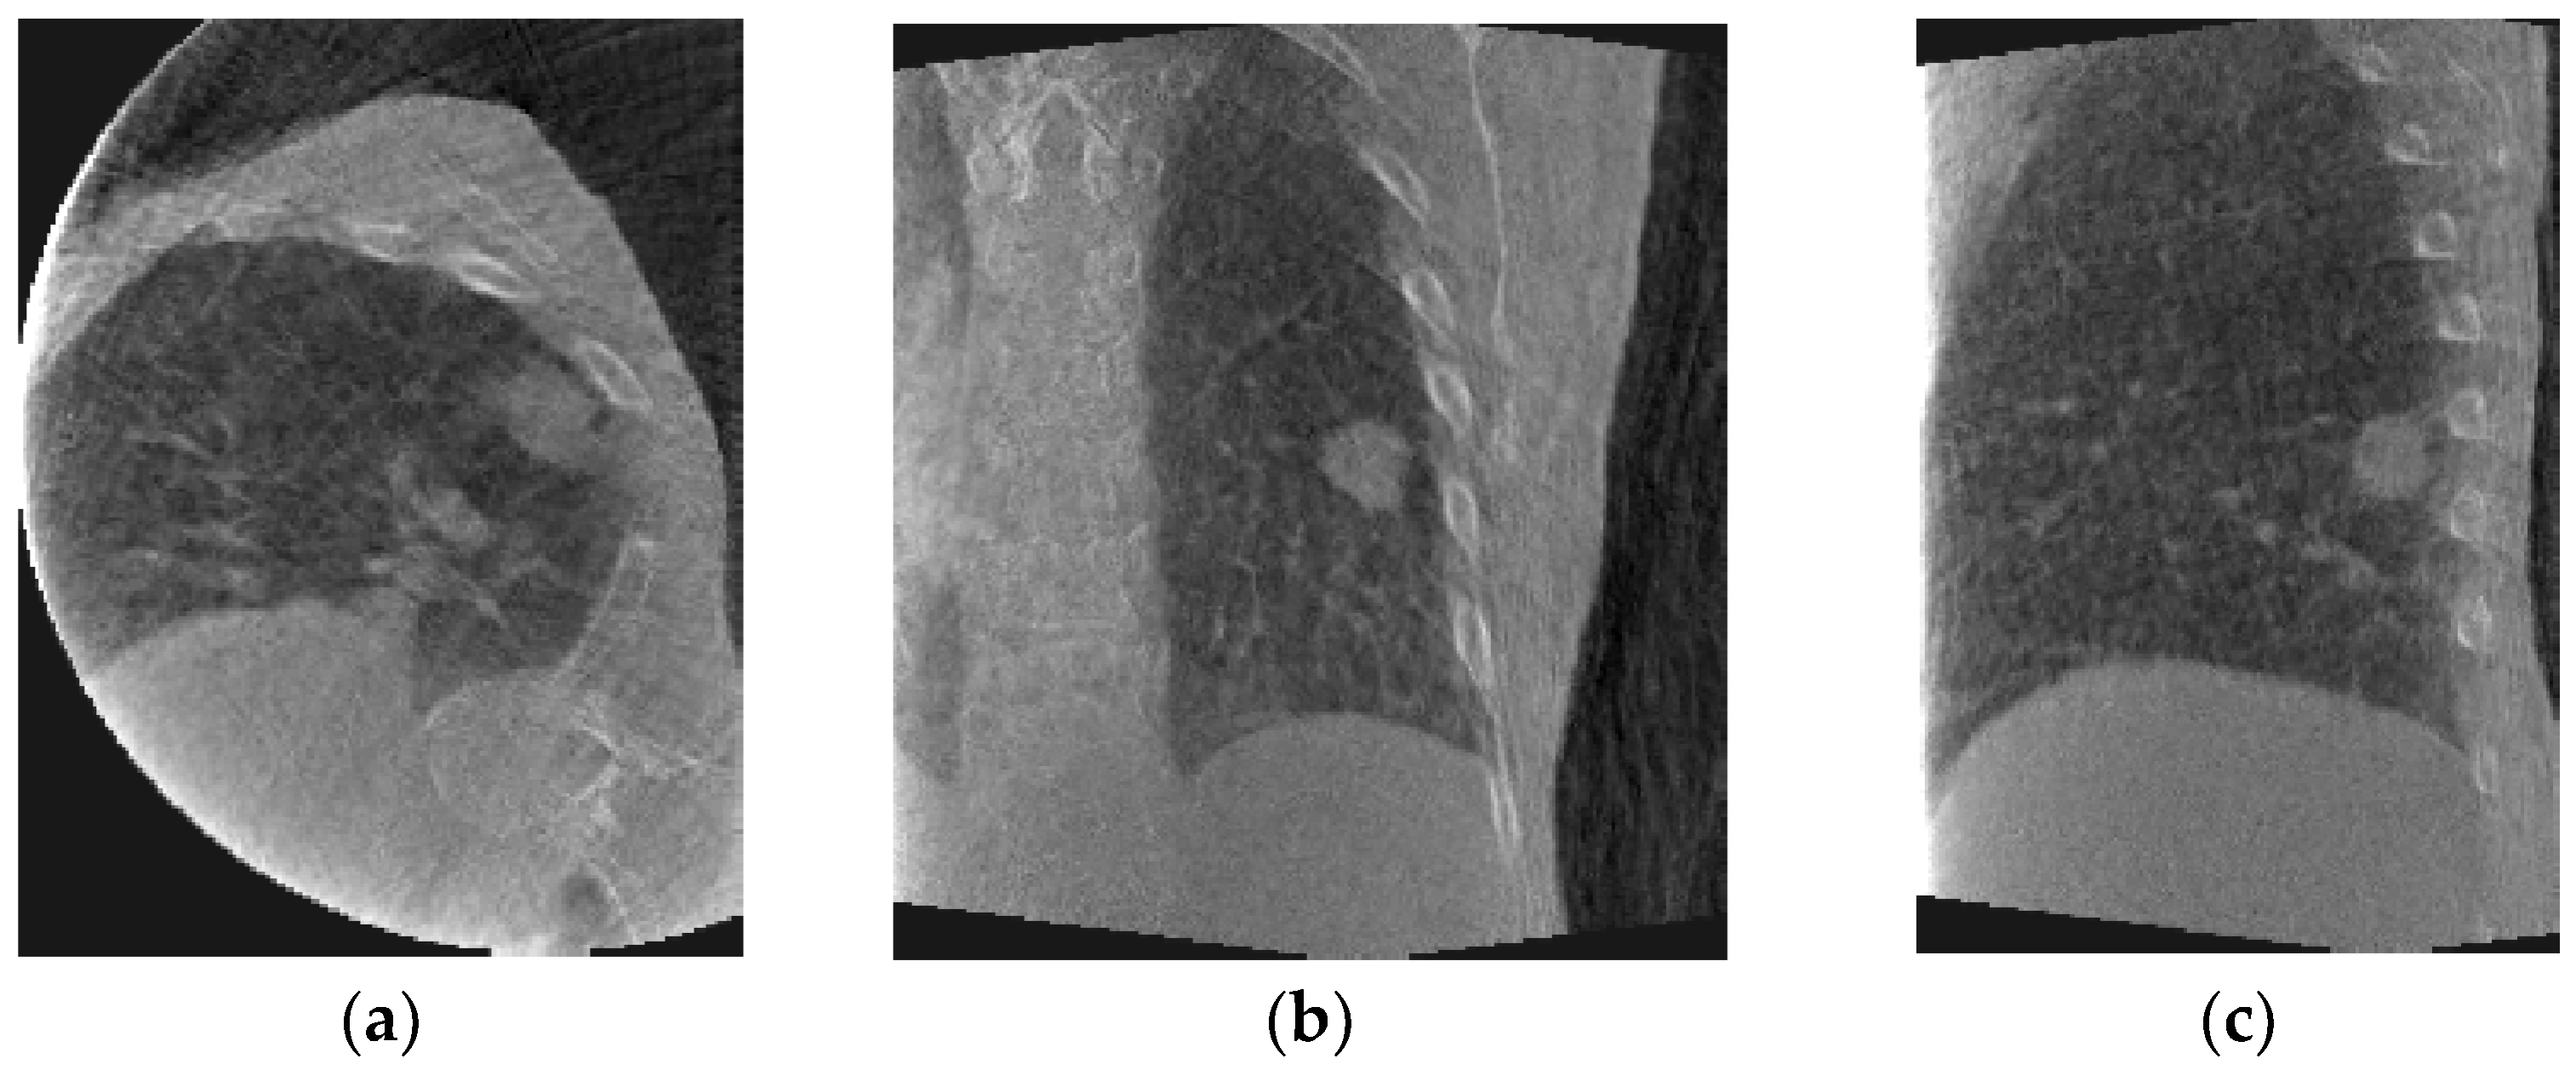

Figure 1 shows axial, coronal, and sagittal slices of peak-exhale 4D-CBCT from each patient. The peak-exhale phase was selected as the reference phase to which all other 4D-CBCT phases are deformed in the DIR module.

Figure 1.

Sample phase (peak-exhale) 4D-CBCT from patient #1 (top) and patient #2 (bottom): (a) axial, (b) coronal, and (c) sagittal slices.